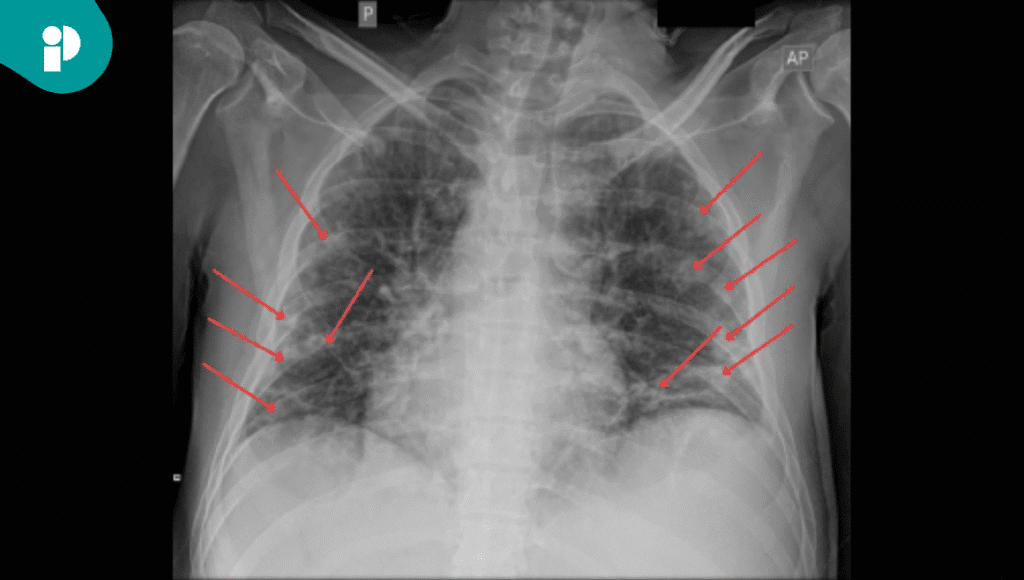

Aunque las pruebas de imagen iniciales sugerían neumonía por Pneumocystis y una embolia pulmonar, la persistencia de los síntomas atípicos y el empeoramiento del paciente llevaron a una ecocardiografía.

Este estudio reveló la presencia de vegetación en la válvula tricúspide, lo que confirmó el diagnóstico de endocarditis infecciosa. Este hallazgo fue crucial, ya que la infección en la válvula cardíaca era la causa subyacente de la asistolia al tragar.